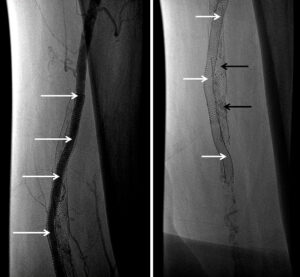

Angiography performed 3 years and 8 months following the procedure demonstrated excellent patency of the DBS (Picture). Interventions were performed at sites other than the double-barrel stent.

Figure 4. Follow-up angiogram at 40 months (new stent shown with white arrows; occluded stent with black arrows)